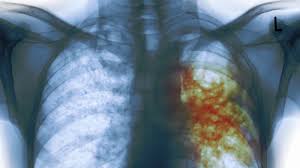

Late reporting of Tuberculosis (TB) to health facilities by infected persons in the Sekyere-Kumawu District is hugely impeding the fight against the disease in the area.

The situation has resulted in the drop of TB treatment success rate, which used to be 100 per cent in 2016, to 75 per cent in 2019.